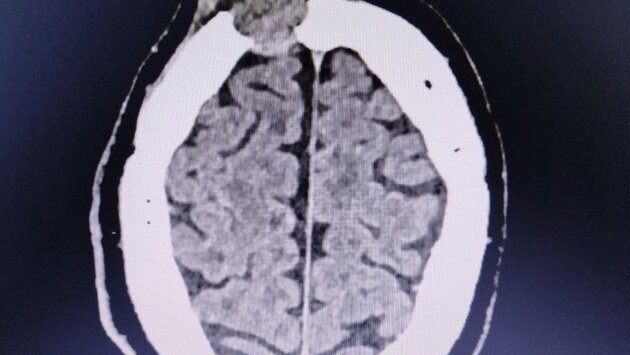

Ранее в ГКБ №7 обратился мужчина, который за три недели до этого ударился и на его лбу выросла шишка. За прошедшее время она не только не прошла, но и немного подросла. Компьютерная томография показала, что это опухоль, которая уже начала разрушать лобную кость. Пациента госпитализировали в нейрохирургическое отделение.

Случай оказался непростым: один край опухоли лежал над самой крупной веной мозга, а другой разрушал стенки лобных пазух. В результате образование создало сообщение между полостью черепа, полостью носа и внешней средой, а это опасно развитием гнойных осложнений.